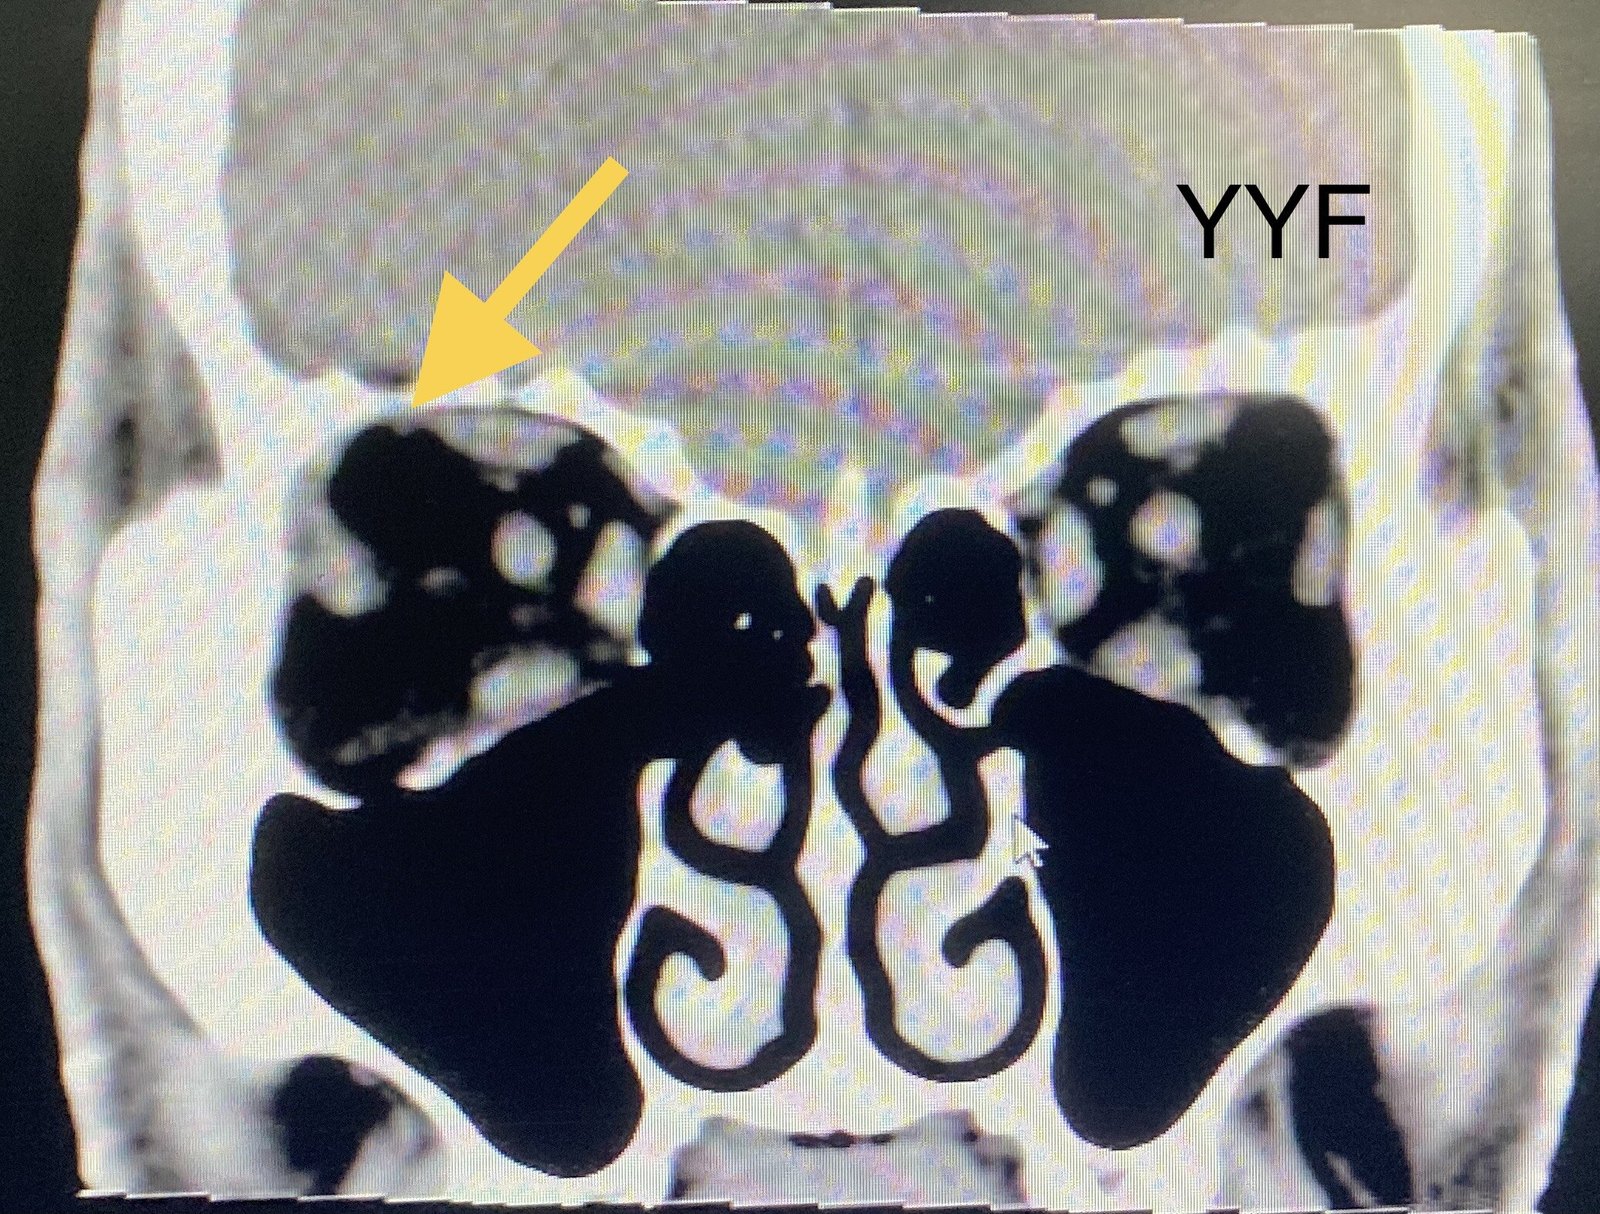

以下图片为病例二 ,完整摘除的随访病例

泪腺混合瘤的核磁共振表现

术后随访很重要,正常泪腺组织也并非全部切除